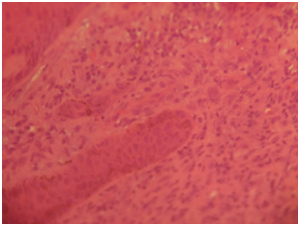

Gross examination showed fragments of gray, white tissue partly covered by skin aggregating 1.8cm. Histological sections showed ulcerated skin tissue exhibiting intradermal monomorphic lymphoid cells infiltrating the epidermis and the adipose tissue (Figure 6) (Figure 7).The cells have round to oval nuclei with the moderate amphophilic cytoplasm. Quite a few cells that have vesicular nuclei with the cerebroid nuclear pattern were noted. Focal areas showing pautriers microabscesses were also present and there is low mitotic activity (Figure 8). The overall features are consistent with Mycosis fungoides.

Figure 6 Photomicrograph shows monomorphic lymphoid cells exhibiting epidermotropism, H, and EX100.